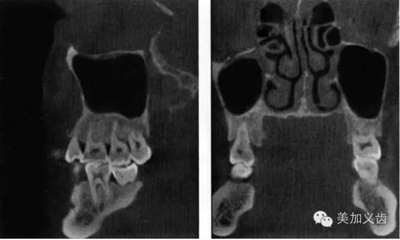

——錐形束CT

這個是三維放射線重建影像可以全面、準(zhǔn)確的評價解剖學(xué)結(jié)構(gòu),包括可用骨形態(tài)的三維數(shù)值,通俗點講就是可以看到可用骨的垂直向、近遠(yuǎn)中向和頰舌向的數(shù)值。

其優(yōu)點是:可以提供精確的、亞毫米級測量數(shù)值,與印模結(jié)合,通過CBCT數(shù)據(jù)來實現(xiàn)模擬手術(shù)并制作外科導(dǎo)板。CBCT的放射量與傳統(tǒng)CT相比要小很多,放射時間短,操作也比較簡單。

9.jpg